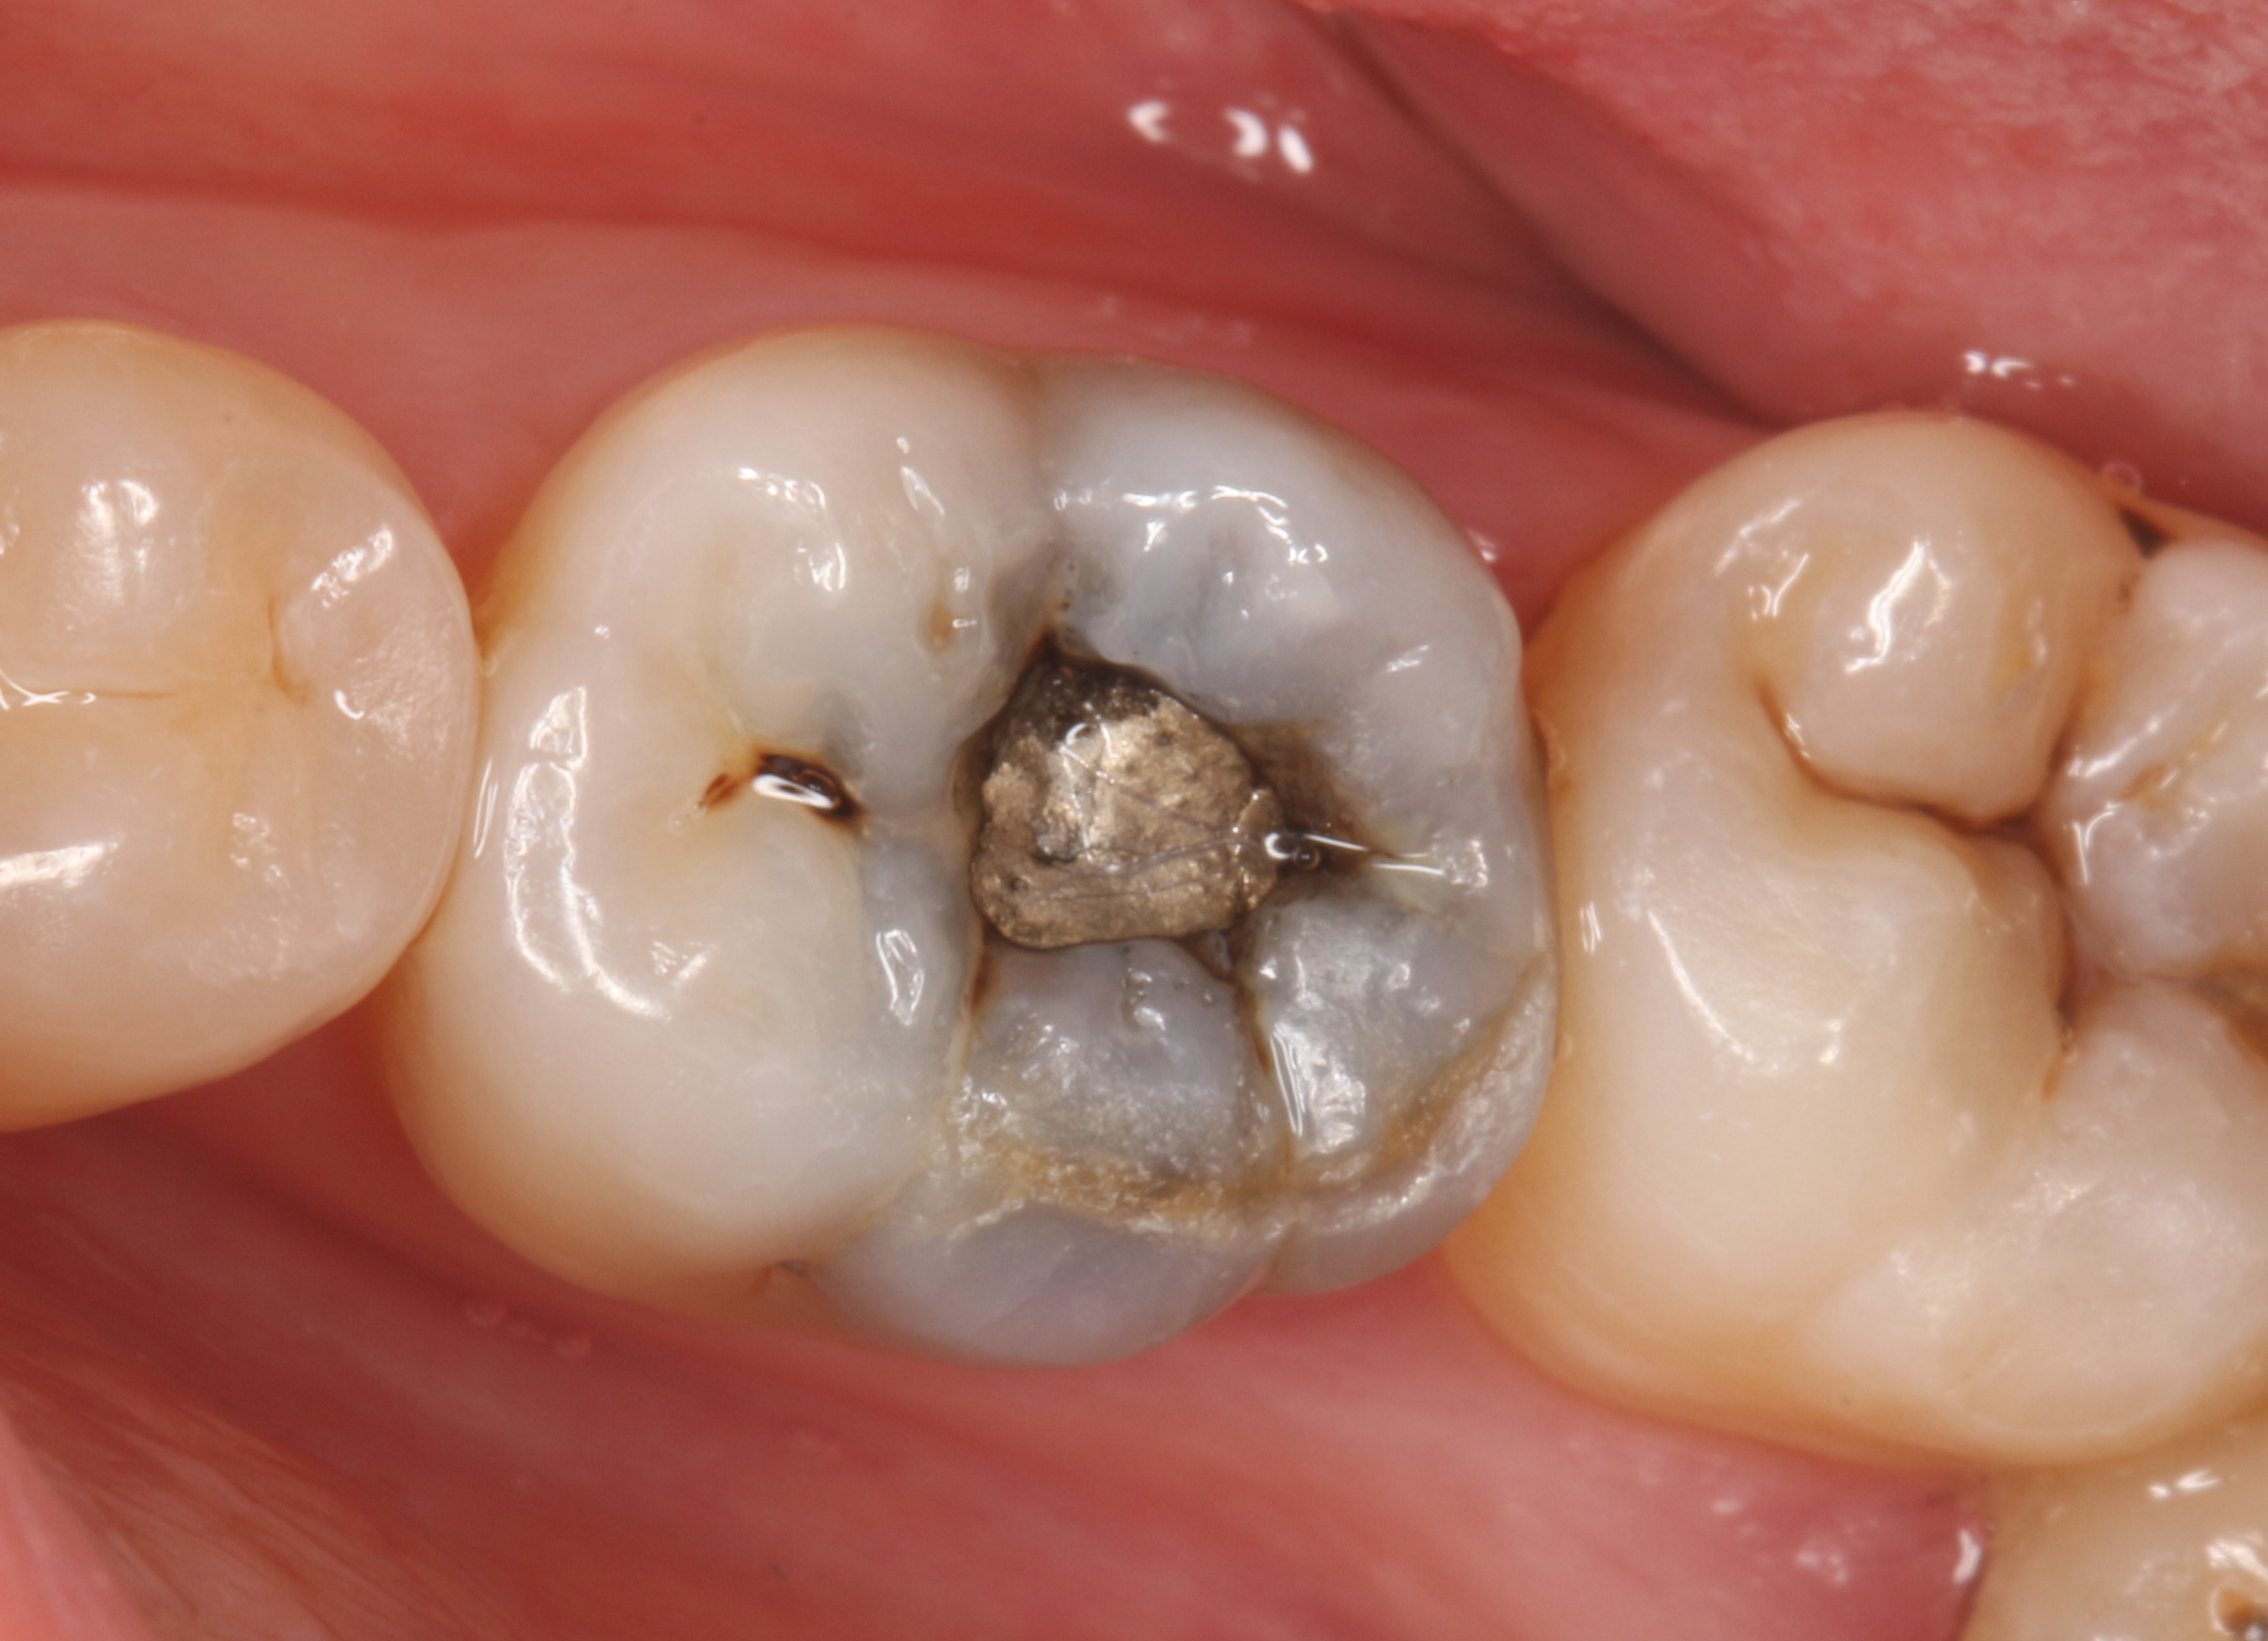

图1 牙齿表面的隐裂纹

图3 牙齿表面是原来补的材料,又产生了蛀牙,但是看不到隐裂纹